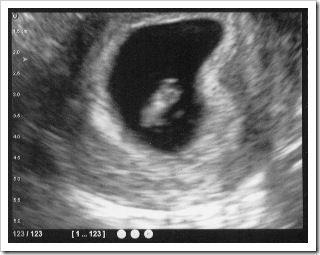

Le jeudi 4 novembre arrive enfin et je me traine lamentablement au rendez-vous. Les nausées sont arrivées et pas qu’un peu ! Genre la super gastro : mal au cœur non stop, vertiges, vomissements 5-6 fois par jour … la balance est en chute libre et mon moral aussi. Après une bonne heure d’attente où nous remplissons une tonne de formulaires, une nurse (infirmière) me prend en charge. Première étape, la pesée. Je peine un peu pour lui annoncer mon poids habituel en pounds … heureusement c’est indiqué sur mon permis. On nous installe ensuite dans la salle d’écho avec grand écran. L’échographe arrive et on voit apparaitre à l’écran un toute petite cacahuète avec un petit point qui clignote. Notre bébé !! C’est juste magique. On n’a donc pas rêvé, il est bien là. Elle le mesure (13mm) et nous annonce une date d’accouchement pour le 19 juin 2011. Tiens ça sera la fête des pères (US et France) ! L’infirmière revient pour les prises de sang. Elle est adorable … j’aime pas les piqures et encore moins les prises de sang … ouais je suis une chochotte ! Le gynéco nous rejoint, fait un p’tit frottis (oh chouette alors !!) et nous explique un peu le suivi. Heureusement que chéri est là parce que je plane un peu et j’ai du mal à suivre la conversation. On pourrait penser que c’est un peu bizarre que mon mari soit présent pendant les examens mais il faut savoir qu’ici, on est recouverte d’une “nappe en papier” qui cache tout (les américaines sont-elles plus pudiques que les françaises ?). Un dernière petite anecdote, ici le spéculum est tiédi avant utilisation … nettement plus … euh … confortable mesdames !

Le 7 décembre nous avons fait l'écho de la 12ème semaine dans un autre cabinet spécialisé dans les grossesses à risque, dans l’enceinte de l’hôpital Holy Cross (là où bébé devrait naitre. Ici elle n'est pas obligatoire mais j'ai préféré la faire pour écarter tout risque de trisomie 21. Je ne suis pas à risque mais je suis une grande angoissée ... et notre assurance couvre cet examen intégralement (hormis $25 de copay). Après 1 bonne heure d'attente avec une vessie au bord de l'explosion (il faut avoir la vessie pleine pour faciliter l'écho), nous entrons dans la salle d'examen et je m'installe sur la table. L'échographe me met une bonne dose de gel sur le ventre ... chauffé le gel, bonne surprise ! Et nous voilà parti pour admirer notre petit bébé pendant un bon quart d'heure. Magique !! L'échographe l'a mesuré dans tous les sens : 6.1cm de la tête aux fesses et une clarté nucale de 1.8mm ... Bonne nouvelle ! Notre petit asticot n'a pas arrêté de gigoter pendant toute la séance, faisant rire la praticienne. Et vas-y que je pédale, croise les jambes, les étend, me retourne, rebondi sur mon "trampoline" perso, remue la tête, me gratouille le nez ... On s'est pas ennuyé, un vrai show ! Son père s'est même inquiété pour plus tard ! Elle nous a aussi montré son cerveau, son cœur, son estomac et sa vessie. Bizarre de voir le Pimousse en tranches ... Malheureusement, il était encore trop tôt pour qu'elle puisse nous dire le sexe. Le mystère est donc resté entier ! Le gynéco est ensuite venu nous voir pour nous dire que toutes les mesures étaient bonnes et si on avait des questions ... vi une petite : où sont les toilettes ? Arf, j'en pouvais plus !!!! Une nurse a ensuite vérifié mon poids, puis m'a piqué le doigt pour récupérer un peu de sang pour le test sanguin de la trisomie 21 et j'ai eu le droit à un beau pansement à paillettes ! Nous sommes ressortis rassurés et avec des étoiles dans les yeux !!